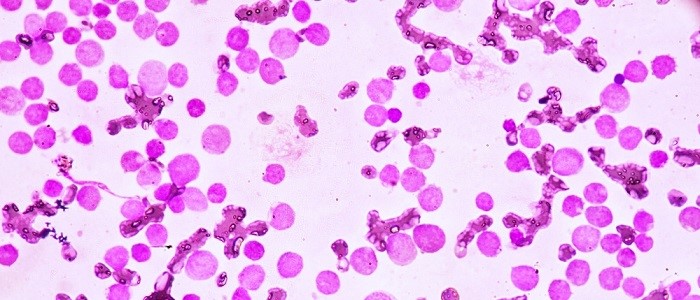

Bioengineered bone marrow model successfully used in leukaemia research